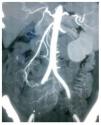

Mujer de 47 años, diabética e hipertensa de larga evolución, con antecedente de nefrectomía derecha por donación cinco años antes. Su padecimiento se inició a fines de 2008 con presencia de evacuaciones hematoquézicas y melena, por lo que requirió múltiples transfusiones. La endoscopia alta y colonoscopia no detectaron el sitio de hemorragia. En agosto de 2009 presentó choque hipovolémico secunadario a hematoquezia (hemoglobina de 3.5 g/dL) que requirió de transfusión de siete paquetes globulares. Se realizaron nuevamente endoscopia alta y colonoscopia que no detectaron en sitio de hemorragia. El gammagrama con eritrocitos marcados mostró concentración anormal del radioisótopo en la flexura hepática. Una enteroscopia no mostró sangrado evidente. Se practicó una angiografía selectiva de arteria mesentérica superior (AMS) en fase arterial (Figura 1), que mostró vasos de neoformación tortuosos e irregulares a nivel de íleon, sin retorno venoso temprano. La angio-tomografía computarizada (angioTC) con reconstrucción coronal y proyección de máxima intensidad (Figura 2), detectó una imagen hipodensa, con vasos tortuosos de neoformación que nacían de la AMS. La angioTC en 3D (Figura 3) reveló múltiples vasos de neoformación dependientes de la AMS localizados en íleon que demuestran una tumoración con gran vascularidad. Se realizó laparotomía exploradora encontrando un tumor a 90 cm de la válvula ileocecal (Figura 4). El análisis histopatológico determinó tumor estromal de alto grado con bordes quirúrgicos libres de lesión, con inmunohistoquímica para CD117 (Figura 5) y S100 positivos.

¿ Figura 2. AngioTC, con reconstrucción coronal y proyección de máxima intensidad. Se aprecia una imagen hipodensa, con vasos tortuosos de neoformación con origen en la AMS.